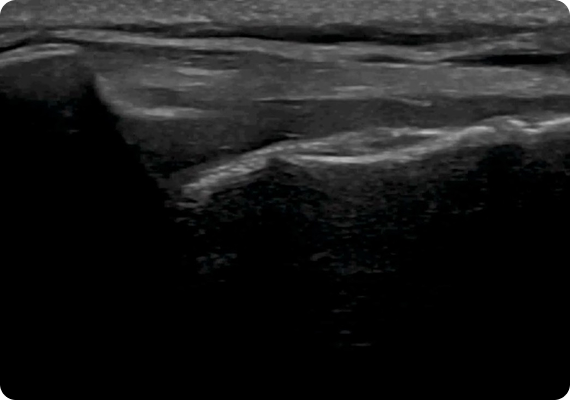

초음파 검사를 통해 어깨 관절낭과 회전근개, 점액낭, 인대 등 심부 구조물의 상태를 실시간으로 확인할 수 있습니다. 이를 바탕으로 염증 부위, 유착 범위, 근육 손상 정도를 정밀하게 파악하여 환자 개개인에 맞는 치료 방향과 재활 계획을 세울 수 있습니다.